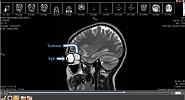

Moorfields Eye Hospital Dubai Performs a Complex Eye Surgery to Remove Massive Orbital Tumour

Moorfields Eye Hospital Dubai, one of the Middle East's leading eye hospitals and a branch of the world renowned Moorfields Eye Hospital in London, has successfully performed a highly complex surgical procedure in which a team removed a large tumour from behind a 26 year old Arab ...